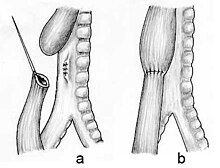

- Les 2 culs de sac œsophagiens sont assez proches : les 2 extrémités sont rapprochables et la continuité de l'œsophage est facilement rétablie sans tension.

- Les 2 culs de sac œsophagiens sont rapprochables mais sous tension, car pas assez proches l'un de l'autre. Risque de suites opératoires plus difficiles.

- Les 2 culs de sac œsophagiens sont trop éloignés l'un de l'autre. Il faut attendre 9 mois à 1 an pour rétablir la continuité en utilisant une autre partie du tube digestif [17] :

- plastie colique si un morceau du côlon (gros intestin) est utilisé ;

- plastie gastrique si c'est un morceau de l'estomac qui est utilisé[3] ;

chacune de ces deux méthodes ayant ses avantages et inconvénients, qui sont pesés par le chirurgien en fonction du type de malformation[3].